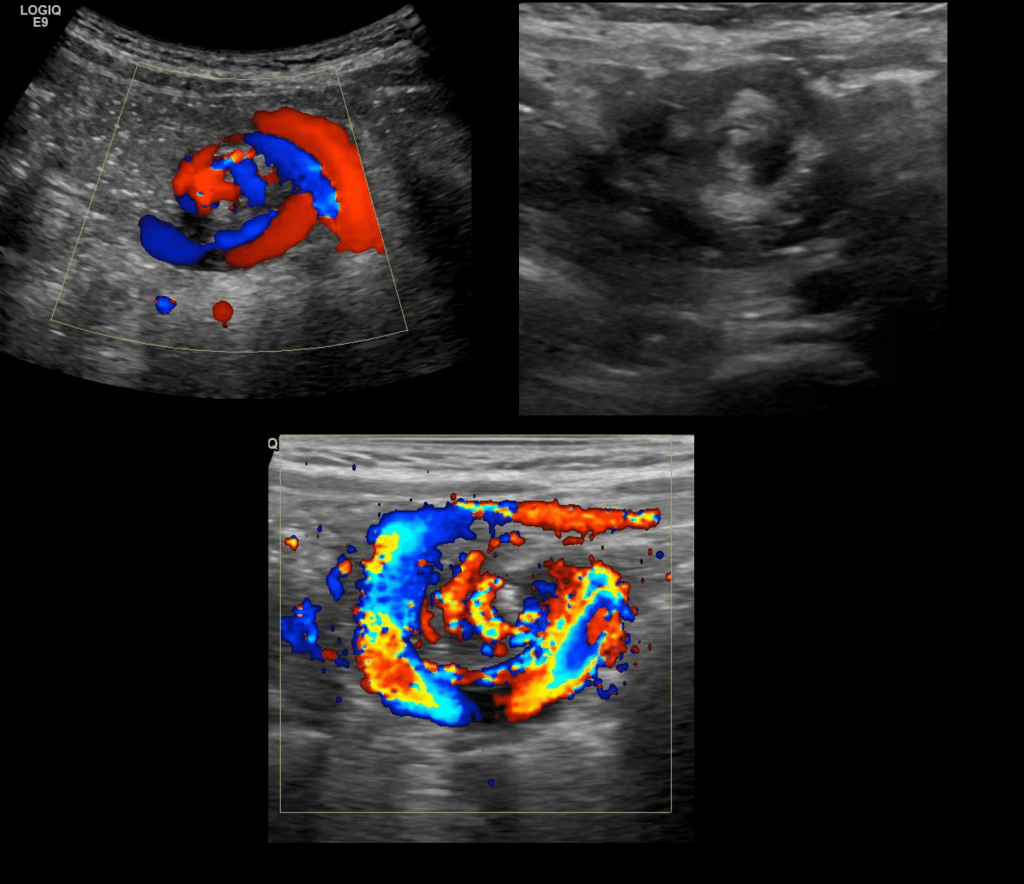

ULTRASOUND FNDINGS

- clockwise whirlpool sign

- abnormal superior mesenteric vessels

- inverted SMA/SMV relationship

- solitary hyperdynamic pulsating SMA

- truncated SMA

- inapparent SMV

- abnormal bowel

- dilated duodenum proximal to the obstruction

- thickened wall of small bowel distal to the obstruction

- dilated fluid-filled loops of small bowel

- free intra-abdominal fluid

IDENTIFYING THE SMA SMV RELATIONSHIP